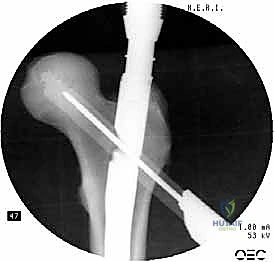

5. تثبيت عنق ورأس الفخذ (المسمار الرأسي)

من خلال ذراع توجيه متصلة بالمسمار الرئيسي، يتم إحداث ثقب في عنق ورأس عظمة الفخذ. يتم إدخال المسمار الرأسي (Cephalic Screw) السميك ليمسك برأس الفخذ بقوة ويسحبه نحو المسمار الرئيسي، مما يضغط الكسر (Compression) ويحفز التئام العظام بسرعة.

6. التثبيت السفلي (Distal Locking)

لضمان عدم دوران العظمة حول المسمار، يتم إدخال مسمار أو مسمارين صغيرين في الجزء السفلي من المسمار النخاعي عبر شقوق جلدية دقيقة جداً (لا تتجاوز 1 سم).